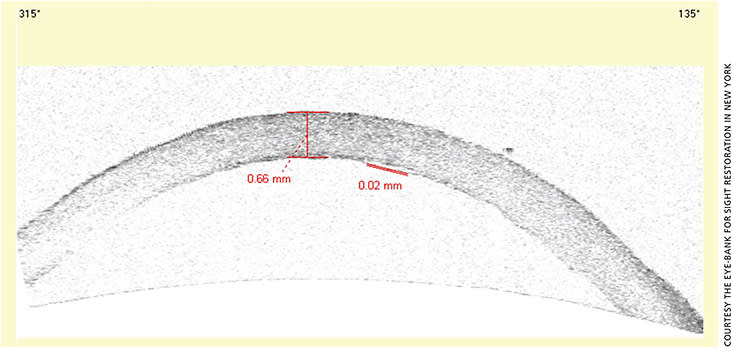

Figure.

OCT image of donor cornea prepared for DMEK.